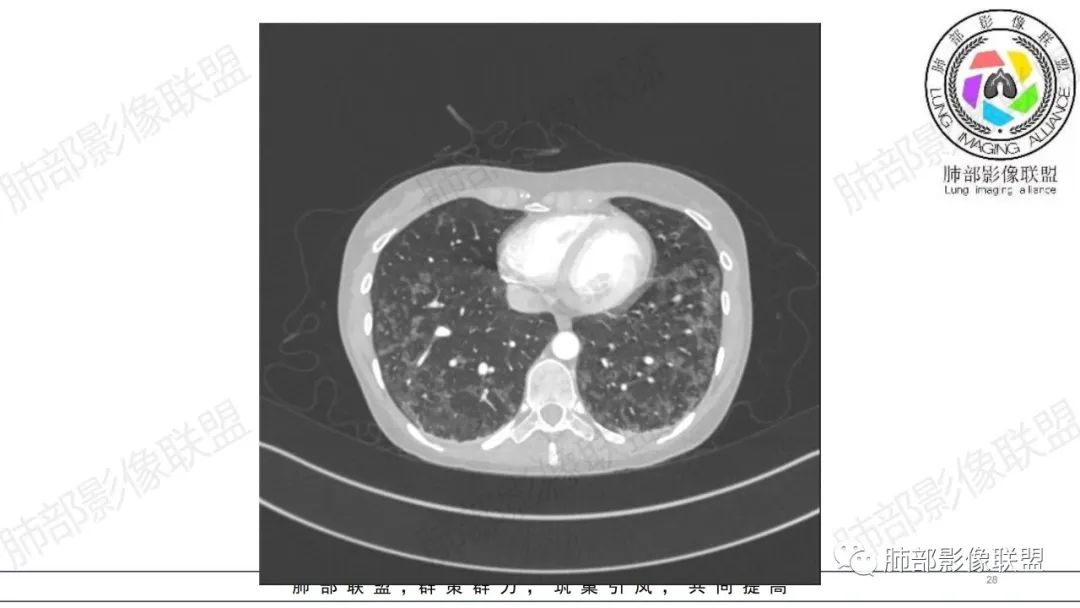

34岁女性患者,“哮喘”病史30年,近期有可疑刺激性气体吸入史;因乏力半年,咳嗽、憋气、发热4天就诊;6.1CT提示双肺广泛毛玻璃影及粟粒样结节,胸膜下闲置及血管周闲置,可见树丫征,部分小叶间隔增厚。考虑:1.过敏性肺泡炎,有可疑刺激气体接触史,胸膜下闲置,广泛毛玻璃影,地图样分布,粟粒结节边界模糊,支持过敏性肺泡炎,但糖皮激素治疗效果不佳,且动态复查血常规血红蛋白进行性降低,过敏性肺泡炎 不符合;2.肺含铁血黄素沉积症:患者30“哮喘”病史,可能为肺含铁症状,肺部CT提示双肺弥漫毛玻璃影及粟粒结节影,中下肺明显,肺底部分小叶间隔增厚,近期咳嗽、憋气、发热,血常规血红蛋白进行性下降,考虑肺含铁急性期症状,但临床无咯血症状,肺含铁不典型。综合考虑:肺含铁血黄素沉积症>过敏性肺泡炎。

年轻女性 ,急性喘息发热,肺部影像弥漫磨玻璃密度,部分细小腺泡结节,胸膜下黑线显示,短期复查,病变密度增高,下肺明显,血管周围肺组织累及较少、且逐渐成小叶间隔分布。考虑弥漫肺泡内病变,并经淋巴道转移,下肺比上肺明显,多为免疫细胞功能下肺较强。1.过敏性肺泡炎,有相关病史,三层密度特点、头尾测分布,符合。2 肺泡微石症,多有钙化,且缓慢起病,病程不太符合,放待排。3 吸入相关肺损伤,有病史,疾病演变过程也符合渗出-肉芽肿改变,建议详细询问病史。4 感染性病变,结核?病变气道分布为主,如此弥漫且没有树丫不符合。5.巨细胞病毒,可以磨玻璃 结节 改变,没有免疫缺陷病史。最后考虑吸入所致 1过敏性肺泡炎、吸入性肺损伤 鉴别肺泡微石症。

肺内气腔磨玻璃结节,肝脾肿大,治疗后间质改变,弥漫大B可能